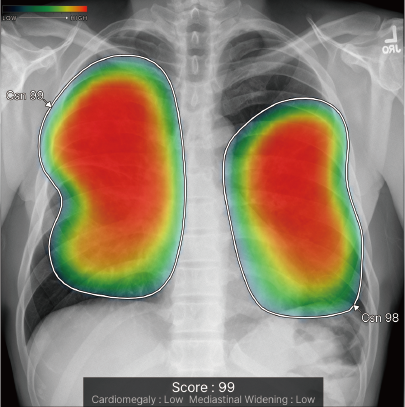

CXR-AIDが候補領域の解析をおこなったのち、0~100に応じた確信度を色分けして表示。

検出領域ごとに所見名を表示します。

対象所見のそれぞれの確信度の最大値が所見ごとに個別に表示されます。

ヒートマップと輪郭の表示は3パターンから選択可能です。